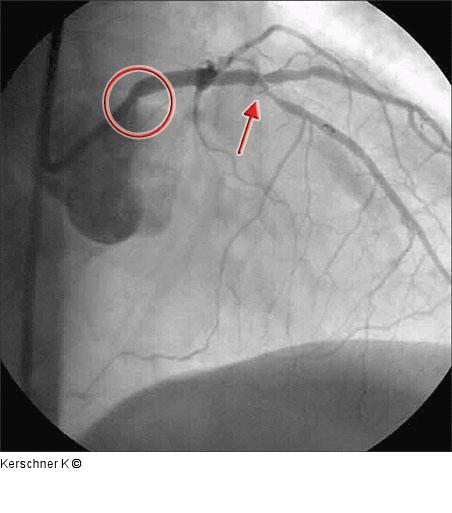

Abbildung 1: Linke Koronararterie RAO/Kranialprojektion 50 % Ostiumstenose Hauptstamm, Bifurkationsstenose LAD – 1. diagonaler Ast (echte Bifurkationsstenose Typ IV ICPS- Klassifikation ), Y-konfigurierter Abgang des Seitenastes. Kollateralen zur verschlossenen RKA. |

Abbildung 1: Linke Koronararterie RAO/Kranialprojektion

50 % Ostiumstenose Hauptstamm, Bifurkationsstenose LAD – 1. diagonaler Ast (echte Bifurkationsstenose Typ IV ICPS- Klassifikation ), Y-konfigurierter Abgang des Seitenastes. Kollateralen zur verschlossenen RKA. |